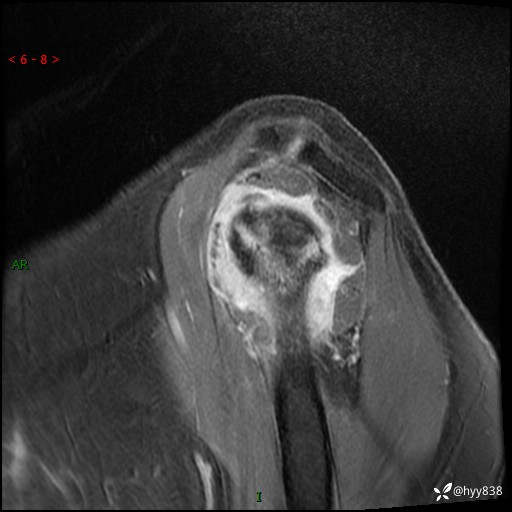

肱骨MRI平扫(axi T1WI+cor T2WI-fs)+CE-fs(COR+SAG)